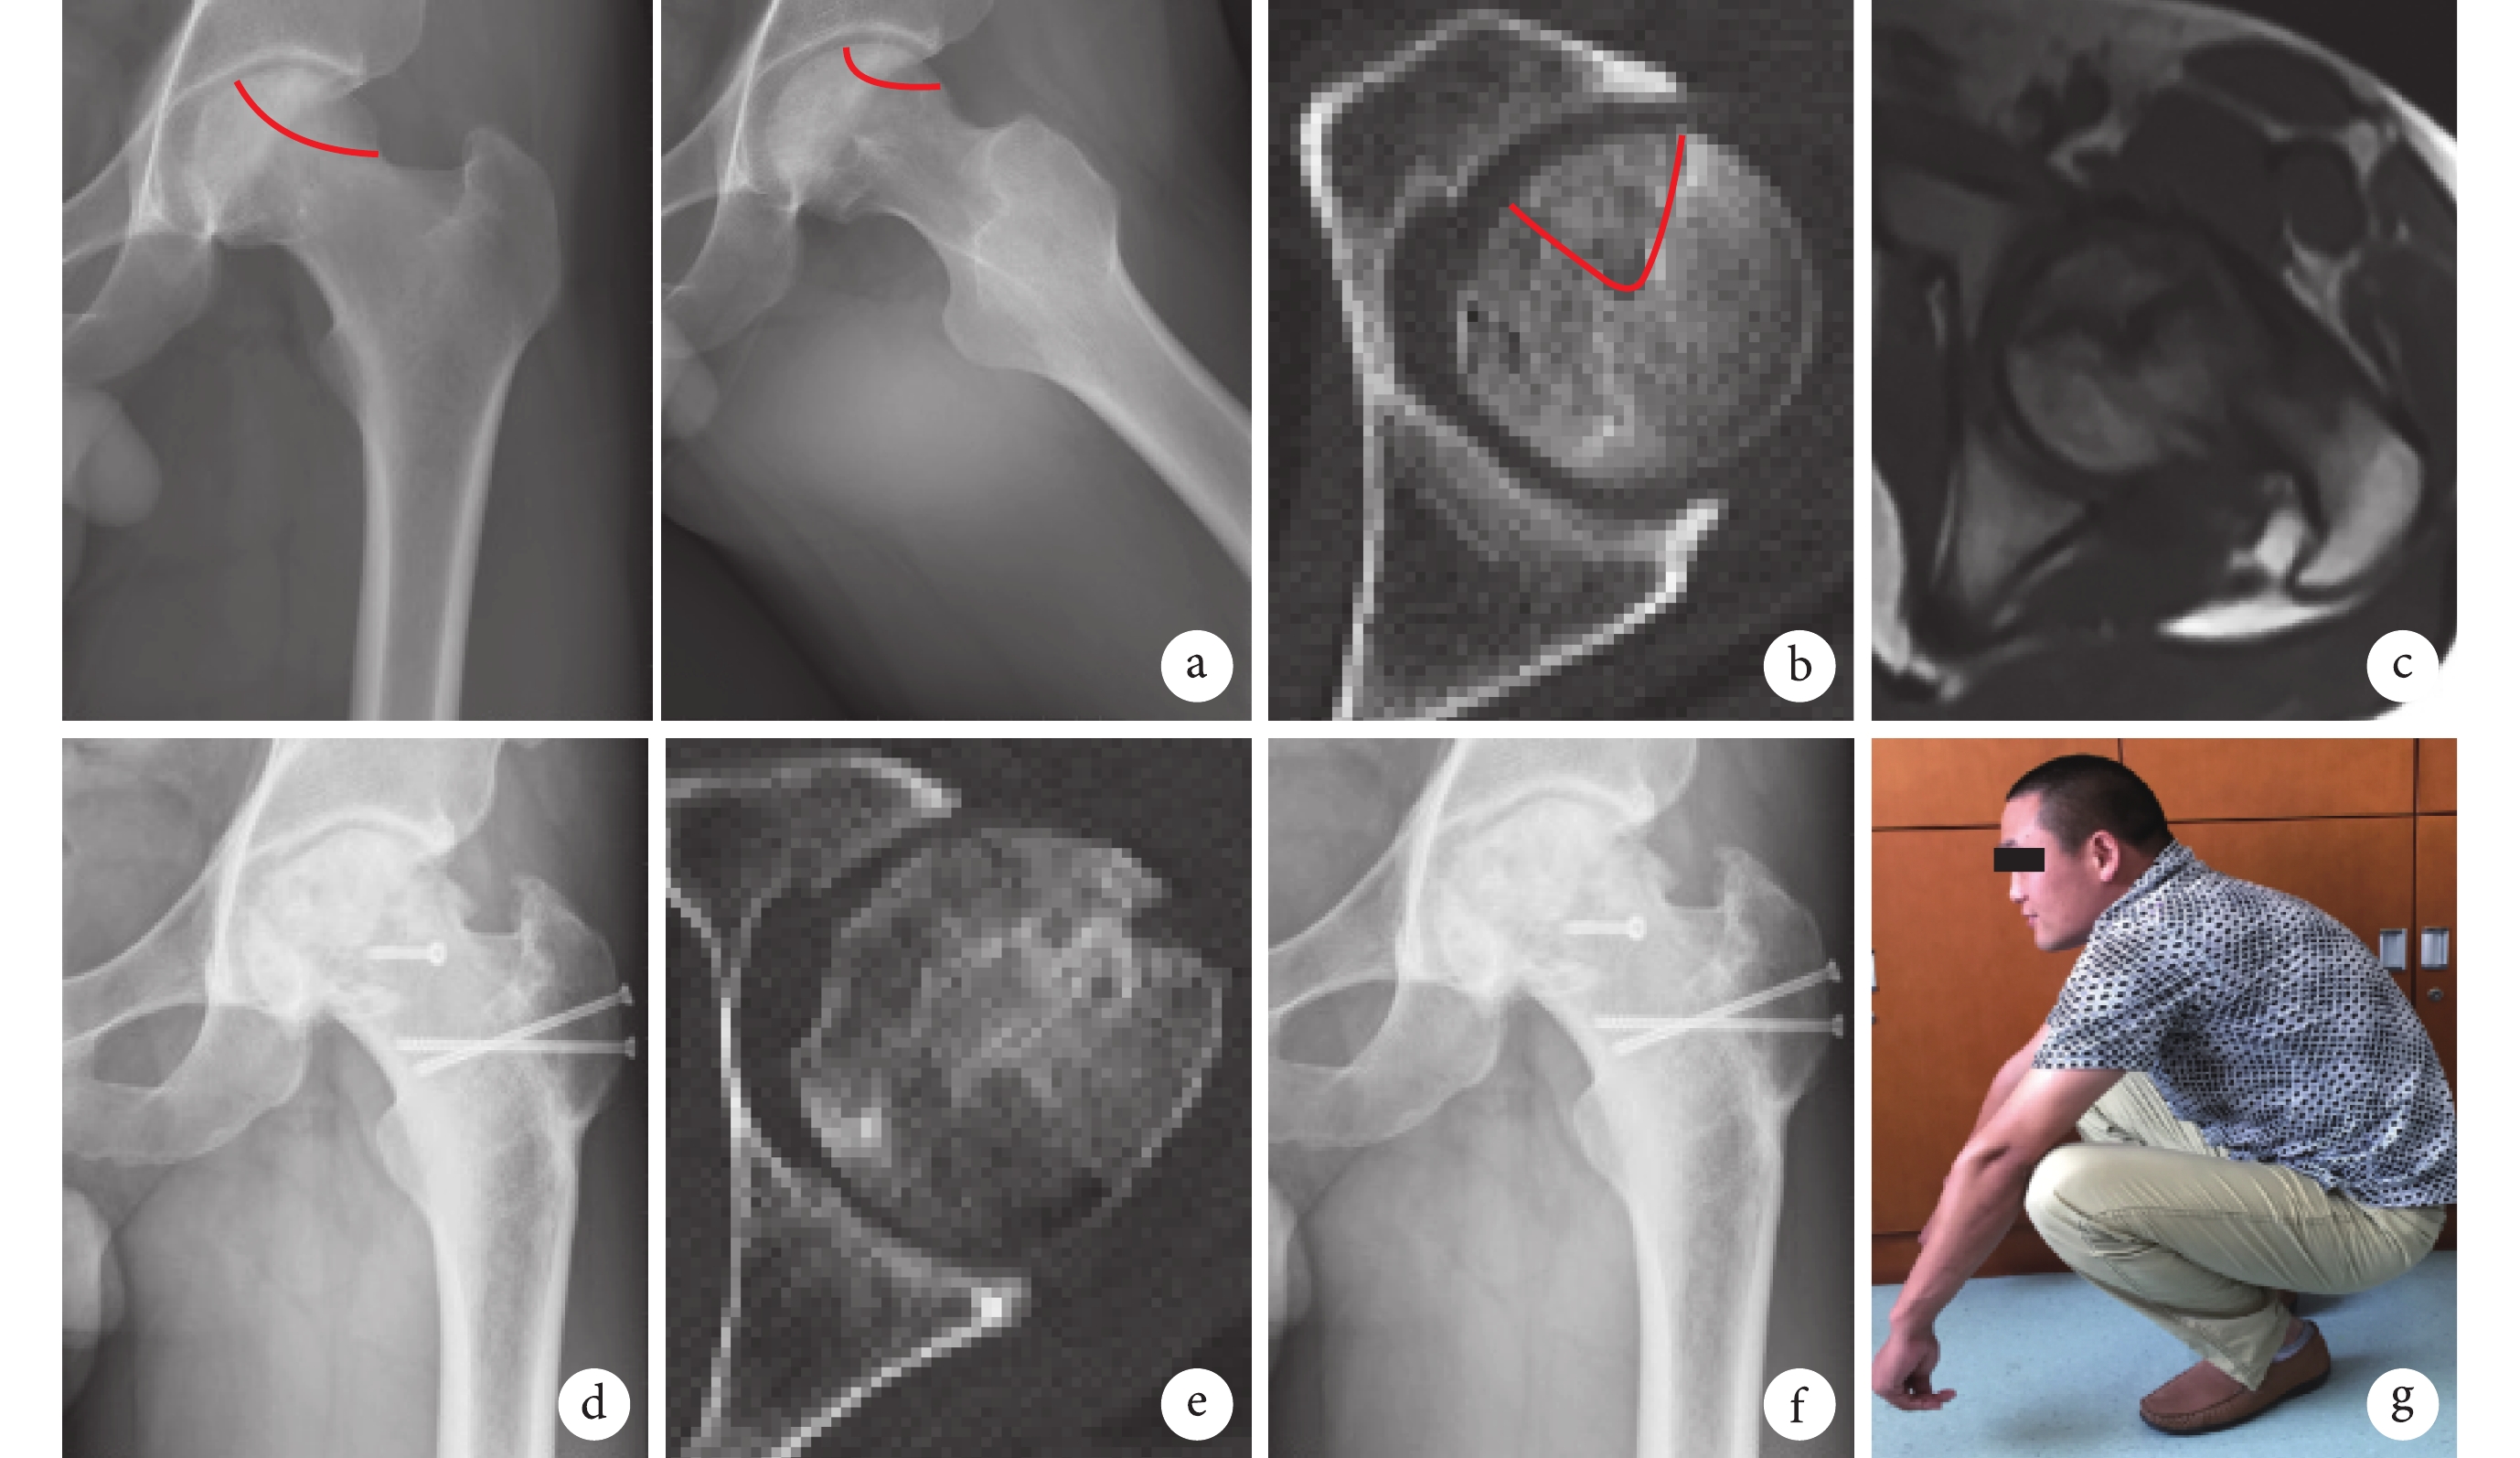

a. 術前 X 線片;b. 術前 CT;c. 術前 MRI;d. 術后 1 周 X 線片;e. 術后 4 個月 CT 示塌陷糾正、植骨愈合;f. 術后 2 年 X 線片示截骨愈合,股骨頭未再塌陷;g. 術后 2 年髖關節功能

Figure4. A 33-year-old male patient with right ANFH (CJFH-L1 type) treated with sequestrum clearance and impacting bone graft via surgical hip dislocation approacha. X-ray films before operation; b. CT before operation; c. MRI before operation; d. X-ray film at 1 week after operation; e. CT at 4 months after operation showed that the collapse retrieved and the bone graft healed with the host bone; f. X-ray film at 2 years after operation showed that the allogeneic fibular graft healed with the host bone and the femoral head did not collapsed; g. Function of the hip joint at 2 years after operation

外科脫位頭頸開窗死骨清理打壓植骨術為本研究小組首次報道(圖 3)[20-21]。目前,本研究小組采用該術式治療 26 例(28 髖)股骨頭壞死患者,其中 CJFH-L1 型患者 15 例(16 髖),平均隨訪時間 13.2 個月,隨訪期間沒有因股骨頭再次塌陷行關節置換治療者,髖關節平均 Harris 評分為 87.5 分,提示外科脫位頭頸開窗死骨清理打壓植骨術治療 CJFH-L1 型股骨頭壞死療效較好(圖 4)。我們認為該術式有如下優點:① 有效保護股骨頭內血供;② 外科脫位后可以直視下徹底清理死骨,并有效打壓植骨;③ 可以在大粗隆截骨區域取自體松質骨用于植骨;④ 大粗隆處血運豐富,利于截骨塊愈合;⑤ 對于合并髖臼頭頸撞擊綜合征的股骨頭壞死患者,外科脫位能夠同時處理壞死和撞擊。